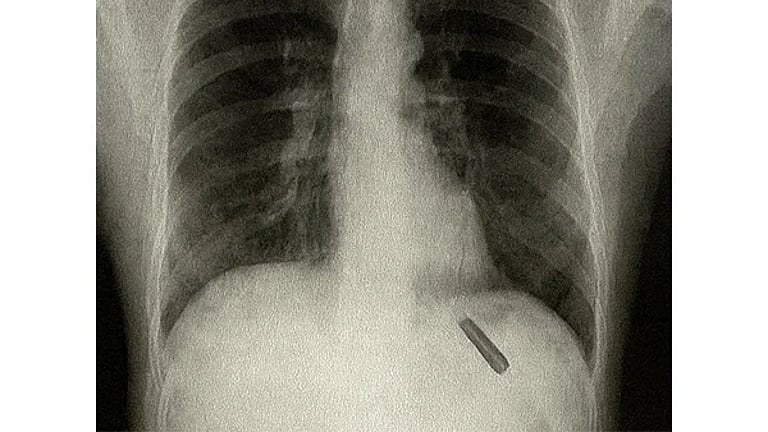

அதிசயமான அறுவை சிகிச்சை: 26 ஆண்டுகளாக நுரையீரலில் இருந்த பேனா மூடி அகற்றம்! 🕑 Mon, 01 Sep 2025

அதிசயமான அறுவை சிகிச்சை: 26 ஆண்டுகளாக நுரையீரலில் இருந்த பேனா மூடி அகற்றம்!

தில்லியில், 26 ஆண்டுகளாக இளைஞர் ஒருவரின் நுரையீரலில் சிக்கியிருந்த பேனா மூடியை மருத்துவர்கள் வெற்றிகரமாக அறுவைச் சிகிச்சையின் மூலம்